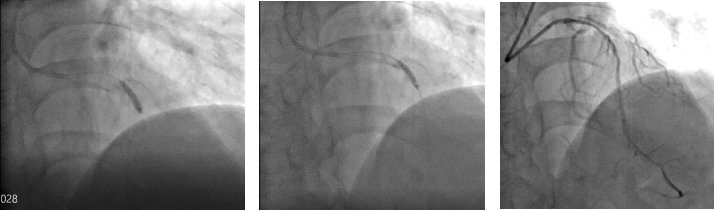

切割扩张后

考虑到目前传统“冠脉内旋磨技术”无法有效解决冠脉深层钙化病变,仔细评估患者病情与适应症后,楚天舒主任当机立断决定使用“Shockwave IVL”新技术处理复杂钙化病变。

冲击波球

在楚天舒主任指导下,团队顺利使用Shockwave IVL震波球囊对钙化病变处进行多个周期的冲击波治疗。治疗中可见冲击波球囊逐渐扩张开顽固钙化区域,冲击波治疗后复查造影可见左前降支近中段的钙化狭窄处明显改善。术中植入的2枚药物洗脱支架在行IVUS中可见支架贴壁和膨胀良好,血管扩张成形满意。术中患者无明显不适,未见低血压、ST改变及心律失常,术后患者胸痛症状明显好转。目前,该患者病情平稳,胸痛症状完全缓解。